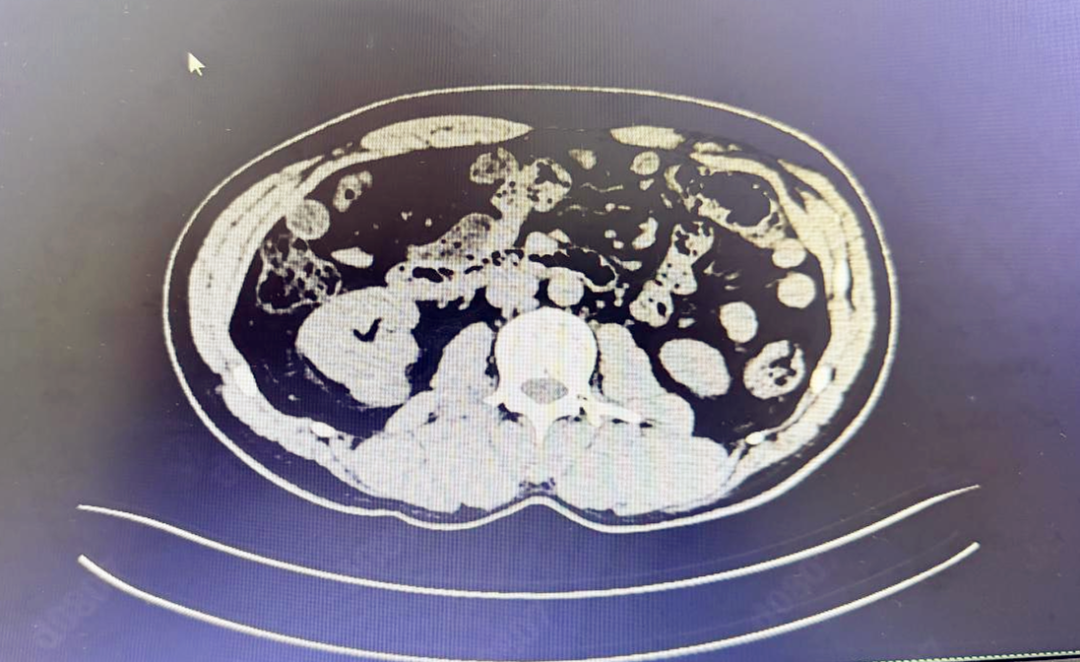

为精准判断病灶情况,科室为陈先生完善肾脏增强CT及MRI检查。影像清晰显示:病灶局限于肾脏某一极,边界相对清晰,恶性病变可能性高,但未出现扩散转移迹象,具备微创手术治疗指征,保肾治疗可行性极高。